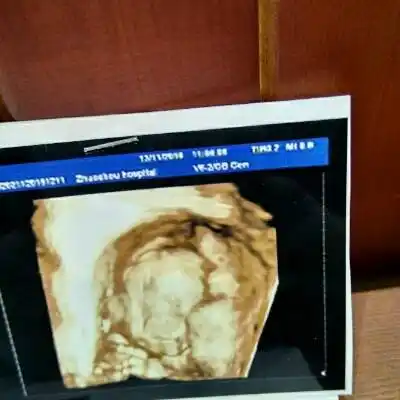

四维一次过,是个儿子

孕24周做的四维彩超,怎么宝宝拍出来的照片,这个样子啊,鼻子大,还有

大家好,帮忙看看宝宝的两次四维照,鼻子是不是好大好塌好短啊,生出来

四维彩超宝宝鼻子大知道四个原因孕妈可以安心了

四维宝宝怎么没下巴

孕期日记23w6三级四维一次通过06